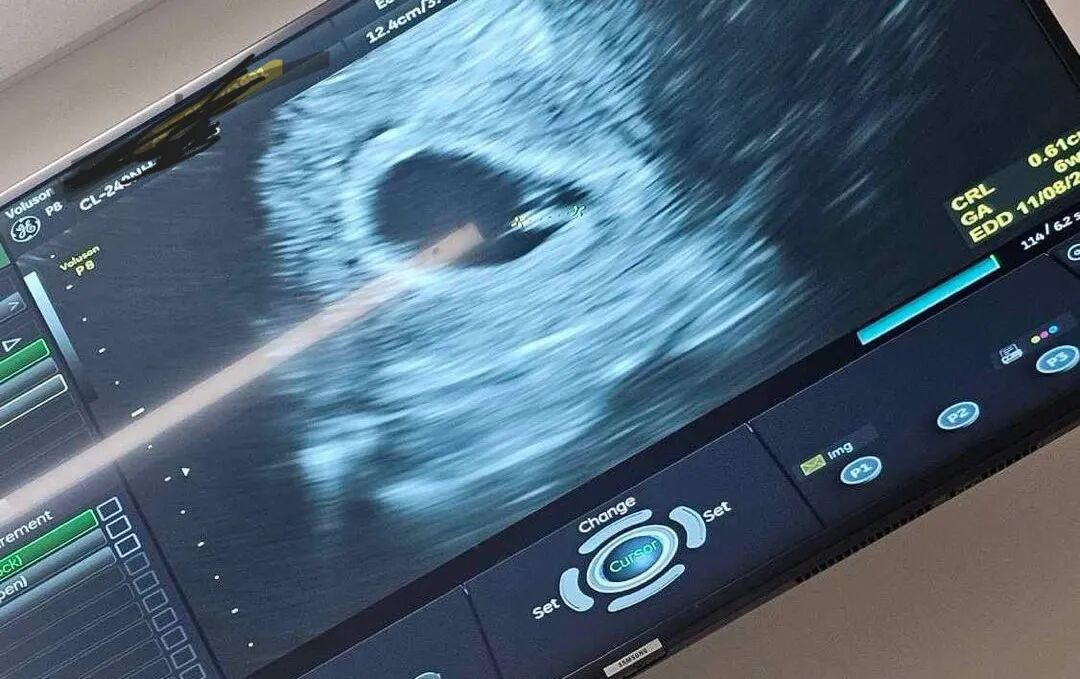

我们单身准妈妈终于迎来了宝宝的喜讯!在我们的帮助下,她找到了心仪的捐赠者,制作出了优质的胚胎。爱妈N特意飞来圣地亚哥的诊所进行移植,一切都进行得非常顺利。今天来诊所进行B超检查,验孕结果成功,虽然宝宝刚刚开始萌芽,但心跳却非常有力,达到了117bpm。我们已经满怀地期待着一个高颜值的混血宝宝的到来了!